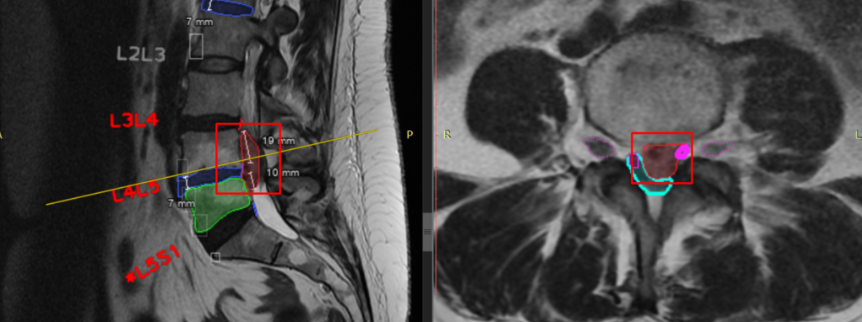

O CoLumbo é um software desenvolvido pela empresa búlgara Smart Soft Healthcare, que utiliza inteligência artificial no pós-processamento de ressonância magnética da coluna lombar. Ou seja, algoritmos de deep learning e técnicas de segmentação automática para identificar estruturas vertebrais, calcular mais de 20 medidas anatômicas, e sinalizar para o radiologista valores fora da faixa “normal”.

A segmentação das estruturas ocorre de forma automática. Imagem a imagem, a inteligência artificial (IA) realiza os contornos. Baseado nas informações carregadas pelo radiologista, o software adiciona, ou não, uma marcação “fora do padrão”. Ou seja, o radiologista pode utilizar valores de literatura, protocolos da instituição ou preferências pessoais, para determinar os padrões a serem utilizados.

- Segmentação automática: a rede neural convolucional (CNN) contorna corpos vertebrais, discos, canal, facetas, etc.;

- Medições geradas: o algoritmo calcula alturas, ângulos, áreas;

- Aplicação de thresholds: compara cada valor com os limites definidos pelo usuário; marca “fora do padrão”;